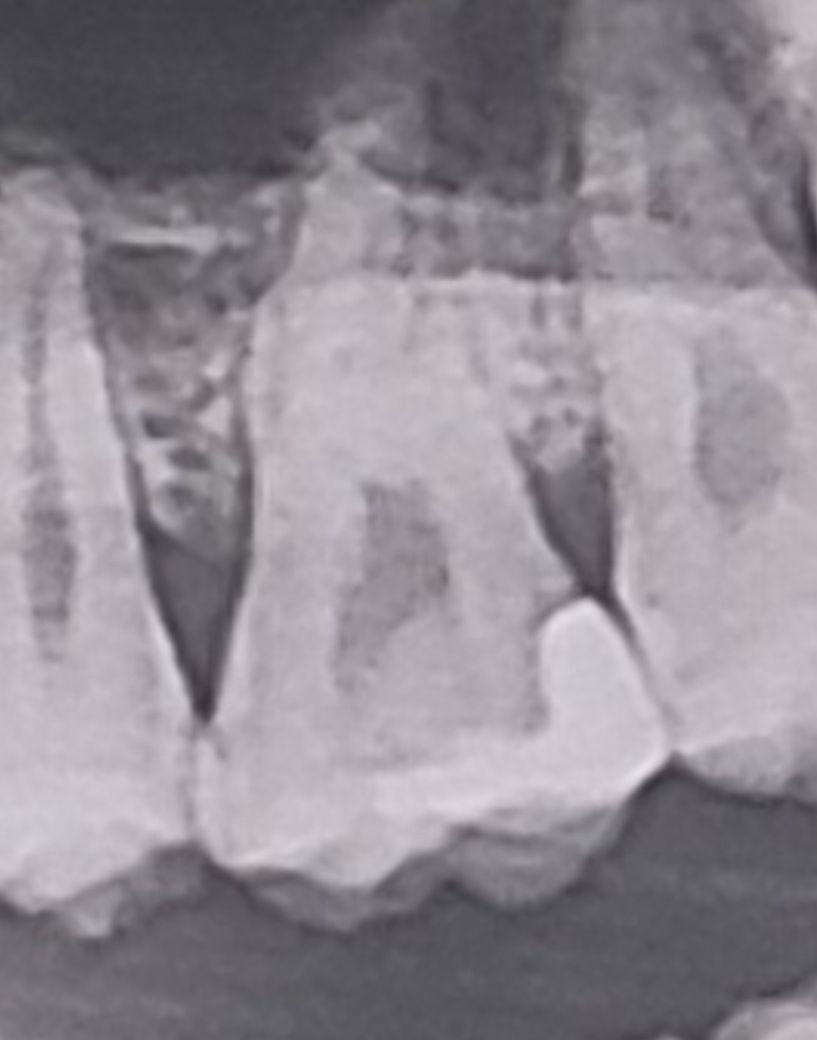

시린 느낌이 드는데 2차 충치인가요?

4월쯤에 치료 받은 건데 이번에 사랑니 뽑으러 다른 곳 가서 찍은 사진이거든요.. 이거 2차 충치 생긴건가요??

사진으로 봤을 경우에는 보철한 부위 주변으로 해서 방사선 음영이 보입니다.

이런 경우 추가적인 충치가 생겼을 가능성이 있습니다. 해당부의 불편감을 지속적으로 생긴다면 보철물 제거하고 내부를 확인해봐야 할 경우도 생길 수 있습니다. 자세한 확인을 위해서 치과에서 진료를 받아오는 것을 권유드립니다.

엑스레이 사진상으로는 이차충치 가능성이 있어보입니다. 치아 사이를 치료하고 나면 음식물이 잘 끼게 되므로 제때 빼주지 않으면 또 금방 충치가 생기고 그렇습니다. 치실이나 치간칫솔을 이용해 관리할 것으로 당부하기도 하고요.